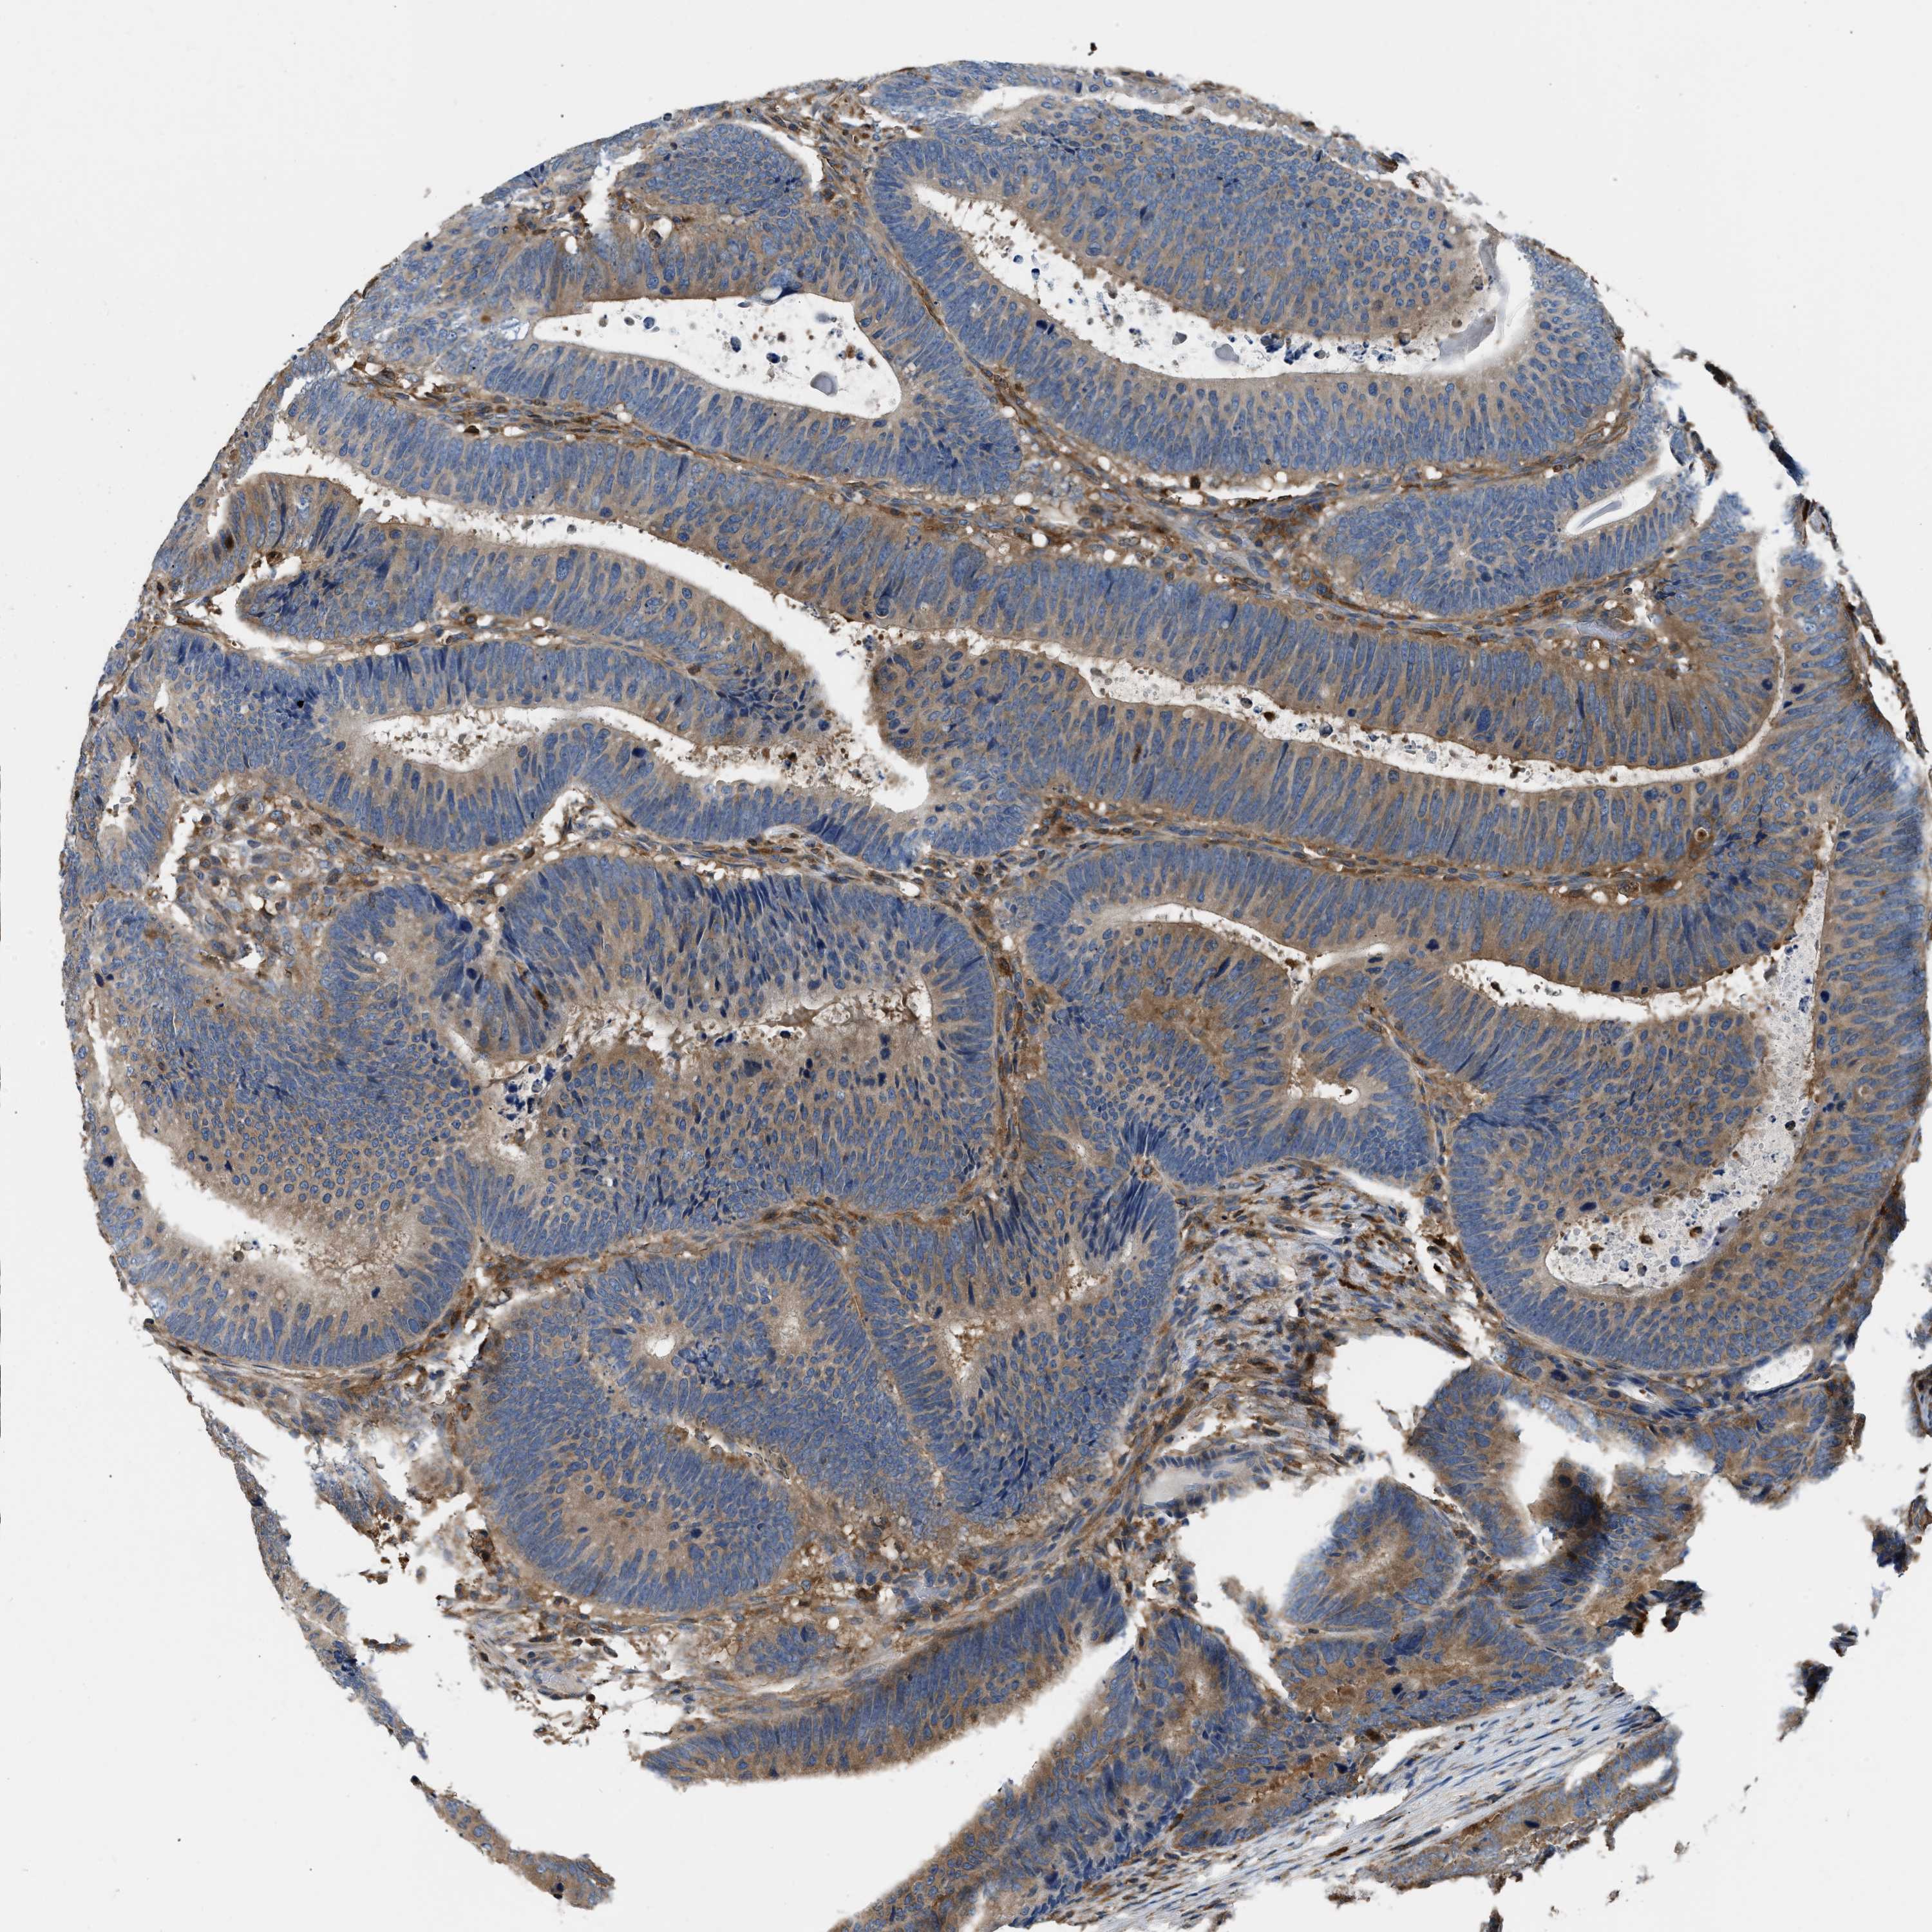

CANCER COLORECTAL CANCER Show tissue menu

Colorectal cancer

Human cancer

Colon adenocarcinoma